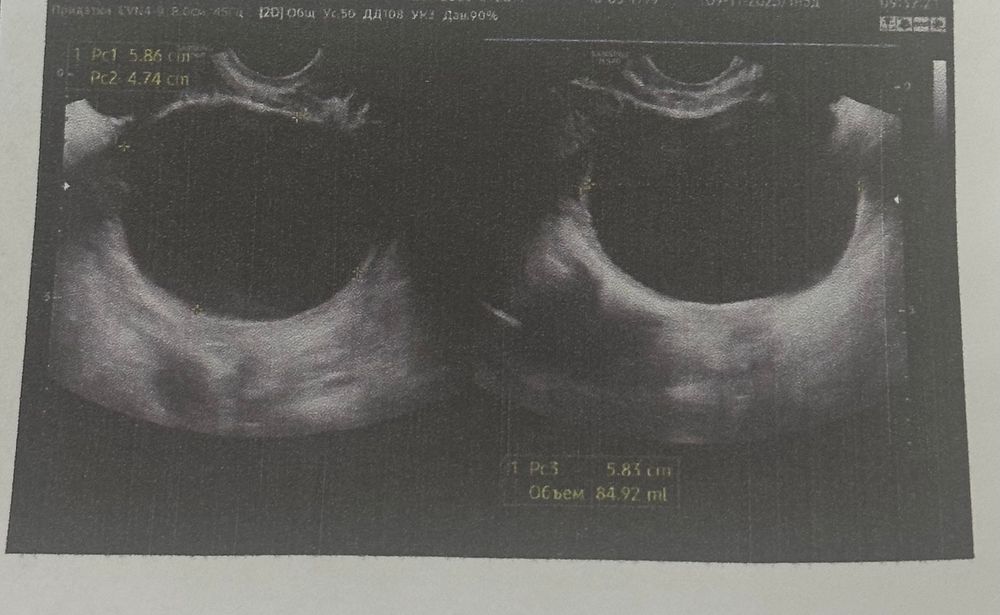

Всем привет. 4 месяца назад на узи обнаружили кисту размерами 6*5 см. Сказали что фолликулярная, назначили лечение. На следующий цикл киста совсем не изменилась, и по сей день она не уменьшилась ни на миллиметр. Что это может быть за киста? У кого было что-то подобное?

Если образование в яичнике не уходит в течение 3х циклов , то делаем мрт. Дифференциальная диагностика с серозной цистаденомой.

Разница на узи в толщине стенки. На обычном аппарате не углядеть. Можно экспертное узи сделать. Но золотой стандарт -мрт. Плюс, сдать на онкомаркеры (са125, he4)

В течение 3х месяцев уже должно было что-то произойти с кистой. Но большие фолликулярные кисты могут существовать до 6 месяцев . потом требуется оперативное лечение и гистологическое исследование .